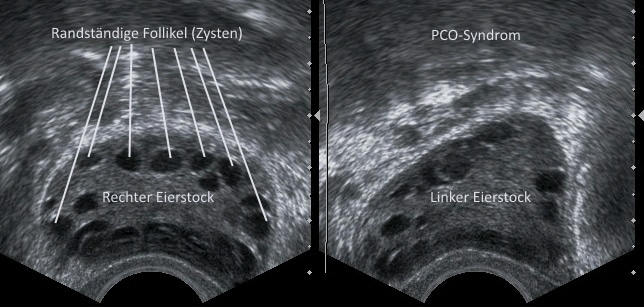

Das #Metformin wird zur Behandlung der #Insulinresistenz verabreicht. Aber auch beim #PCO-Syndrom kann es helfen. Bei der künstlichen Befruchtung und PCO ist es wohl in der Lage, die Risiken für ein Überstimulationssyndrom zu verringern #IVF https://t.co/Q7Es8kzsXB

Hilft Metformin bei #PCO und #IVF? Insbesondere im Zusammenhang mit dem sogenannten PCO-Syndrom hat dieses Medikament seit einigen Jahren ein neues Einsatzgebiet. Verbessert es die Chancen bei der künstlichen Befruchtung? #Insulinresistenz #Metformin https://t.co/Q7Es8kzsXB